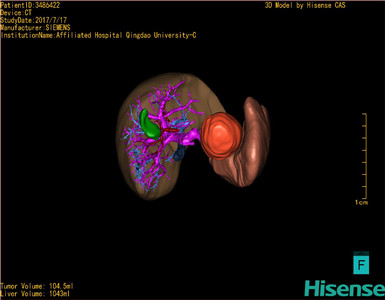

术前三维重建及手术方案设计:

将0.625mm双源薄层CT资料的静脉期和动脉期Dicom格式文件导入海信CAS系统。

通过调节窗宽窗位调整CT序号,对肿瘤,肝实质,胆囊,下腔静脉,肿瘤,肝动脉、门静脉及肝静脉等进行三维重建;系统自动计算肿瘤体积和肝脏体积。

模拟手术操作,自动计算切除肿瘤体积。肝脏体积为1096ml,胰腺肿瘤体积为115.5ml,通过比对12-13岁正常肝脏体积为1116.86±158.78 ml,通过术前模拟手术,精准判断切除后肝脏体积无明显变化,避免肝衰竭发生。

术前三维重建:

重建图片